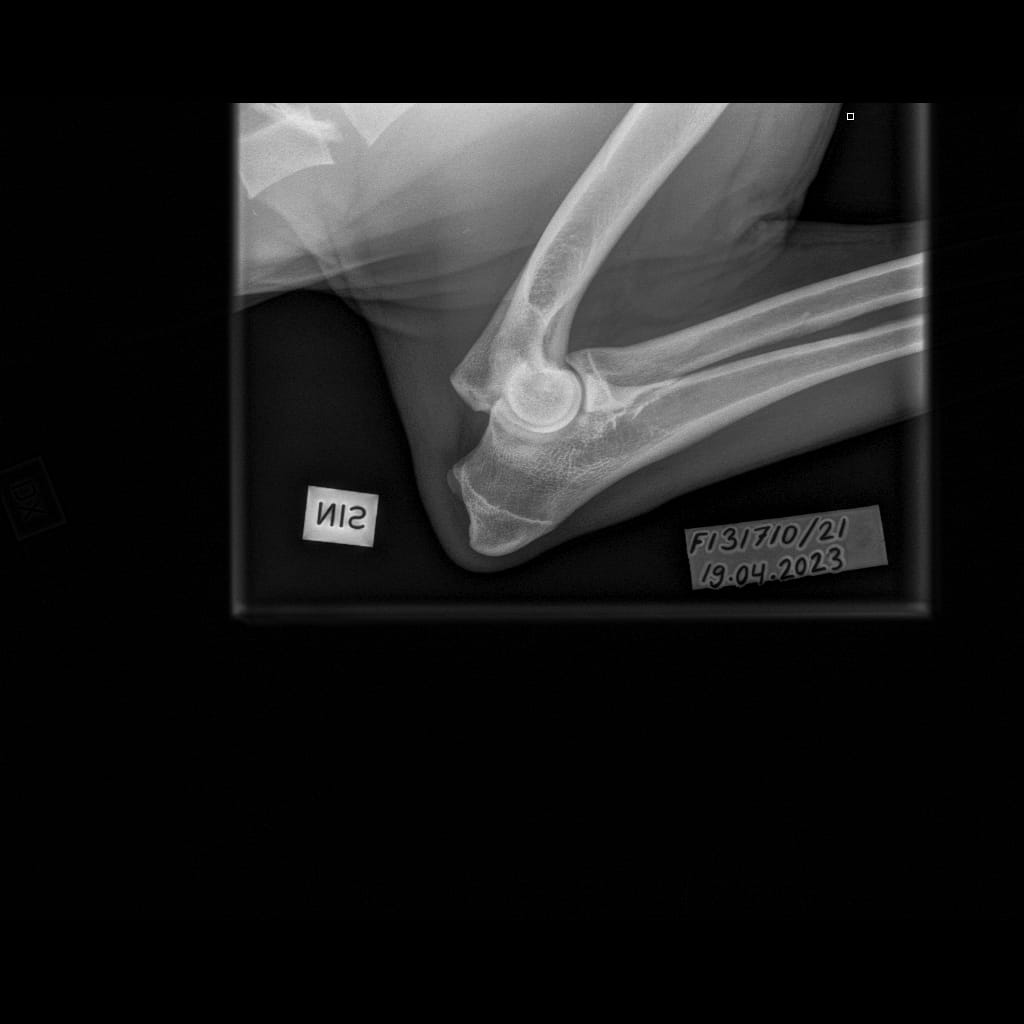

| Elbows: | 0/0 | ||

| Elbows: | 0/0 |

| Elbows: | 0/0 | |

| Elbows: | 0/0 (xray), 3/1 (CT) |

| Elbows: | 1/1 | |